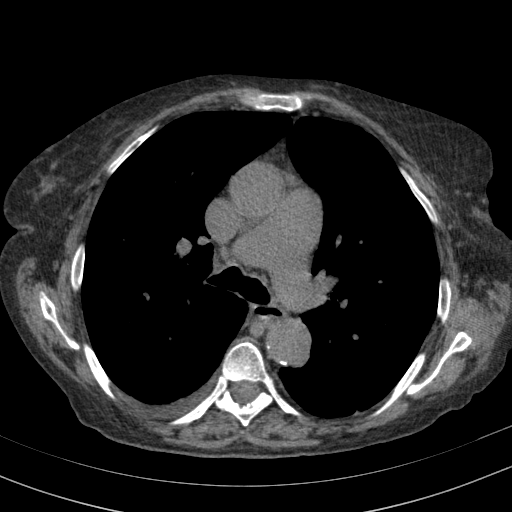

Original VENOUS CT scan

Full window (WL 1023.5, WW 4095 β†’ Low βˆ’1024, High +3071)

Lung window (WL -600, WW 1500 β†’ Low βˆ’1350, High +150)

Mediastinum window (WL 40, WW 400 β†’ Low βˆ’160, High +240)